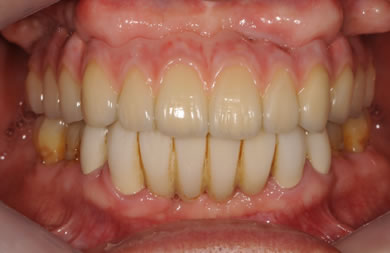

骨再生スピードインプラント治療+AGC連結セラミック治療+セラミック治療

| 治療方針 | ソケットリフト法により上顎洞底部を拳上することにより、骨の無い部分に骨をつくってあげ、インプラント治療を可能にする。さらに歯周病により組織の破壊が著しいので、AGC連結セラミック治療により上顎の審美的回復を行う。 | ||||||||||||||||||||||||||||||||

| 治療内容 | インプラント7本(抜歯AGC即日スピードインプラント+ソケットリフト)、AGCハイブリッドセラミック連結ブリッジ1装置(上顎)ハイブリッドセラミック8本 | ||||||||||||||||||||||||||||||||